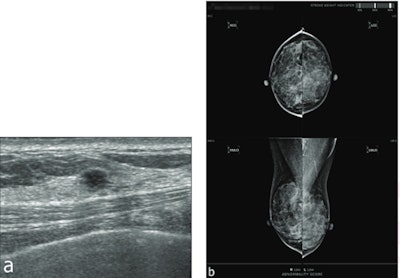

However, AI did have its wins in the study. Although overall sensitivity between mammography and AI was not significantly different, AI detected one invasive ductal carcinoma and one DCIS that were missed on mammography. The researchers reported that one of these missed cancers was visible on mammography in a retrospective review.

AI, however, also missed three cancers, including one DCIS that showed grouped microcalcifications on mammography and two cancers deemed to be occult retrospective mammographic review but visible as masses on ultrasound.